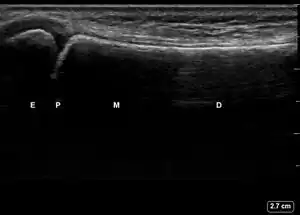

| 2 | Obtain, label, and save an image of the epiphysis (E), physis (P), metaphysis (M), and diaphysis (D). | ![]() | |